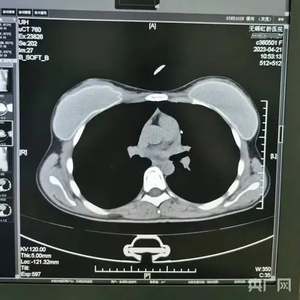

比如,被举报的患者中,72岁的“杨某某”、62岁的“邱某某”的病历中,有根据所拍片子的情况作出的诊断,却找不到对应的影像。6月份又查到了她们的CT影像,按照系统记录,她俩都是2023年4月做的胸部CT,片子上能清晰看出两位患者的吊坠形状、大小和位置都基本一致。不仅这两位上了年纪的患者,CT影像类似,朱成刚比对发现,2021年在他们科做过CT的25岁女性叶某的片子上,也有看起来极为相似的吊坠,肉眼看,她们三人的片子几乎一模一样。

放射科知情人士李医生告诉记者:“这个人叫邱某某是个假的(病历)62岁,这是它的假图像,哪里像62岁的女性?项链的吊坠咱都看到了,看到它的特色了,杨某某这个72岁,女,看图像是一个人不是?”

类似这样看上去雷同程度很高的片子,还有不少。比如系统显示,患者李某某在2023年4月28日拍摄了胸部CT,她的影像与实际患者刘某在2024年2月的检查影像看起来高度相似。74岁的患者莫某在2023年4月27日拍了胸部和颈椎的CT,她的片子看起来和实际患者37岁的马某某在2023年11月拍的片子高度相似,片子里能直观看到项链都一模一样。